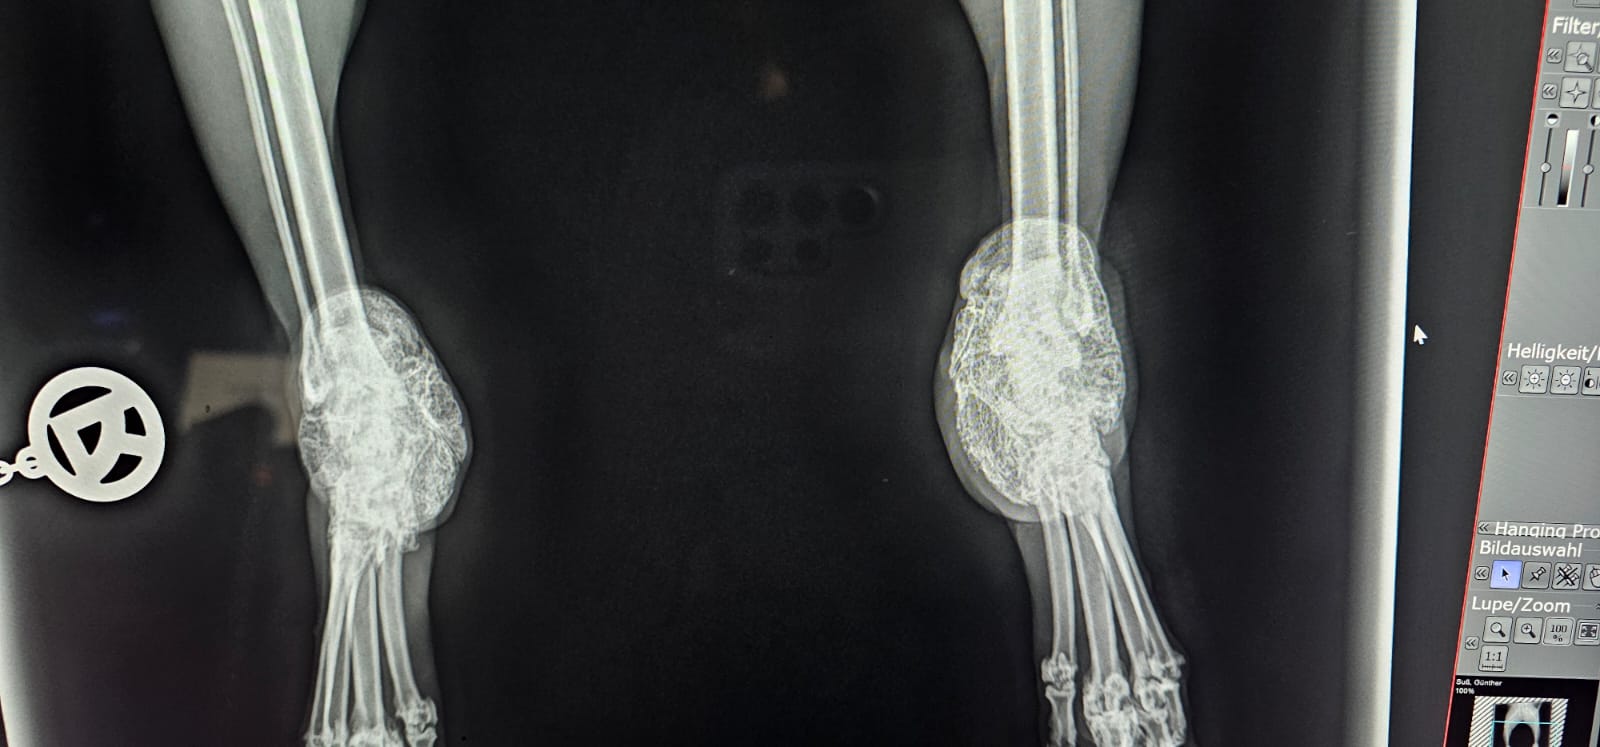

Scottish Fold

Der Gendefekt betrifft den gesamten Knorpelapparat.

Folgen:

- chronische Gelenkschmerzen

- Versteifungen

- Lahmheit

- eingeschränkte Beweglichkeit

Viele Katzen zeigen Schmerzen erst spät – wenn sie nicht mehr springen oder sich zurückziehen.